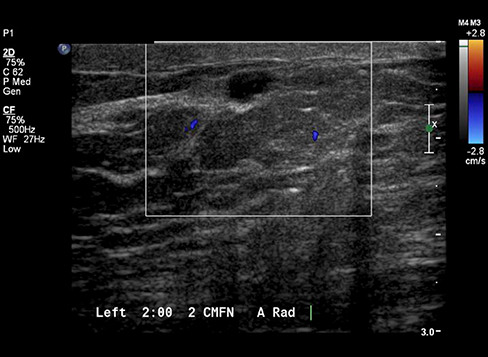

Case Example 3:

24-year-old female presents with a 2.7 cm palpable mass in her right breast. Ultrasound imaging demonstrates a solid mass with negative color doppler.

Case Example 3: Observations

The mass does not reveal any suspicious internal signal on the combined map with paired draping vessels anteriorly and a deoxygenated vessel posteriorly. Draping vessels are typical benign characteristics when seen in OA, as the mass pushes the vessels away versus penetrating or feeding the mass in a cancer OA image.

Balanced mixture of well-organized red and green vessels, small in size with large periphery vessels as seen in the OA Relative map.

- No biopsy - LOM BI-RADS 2

- Fibroadenoma

Mass down-classified from BI-RADS 3 to BI-RADS 2. Typical OA characteristics seen in fibroadenomas.